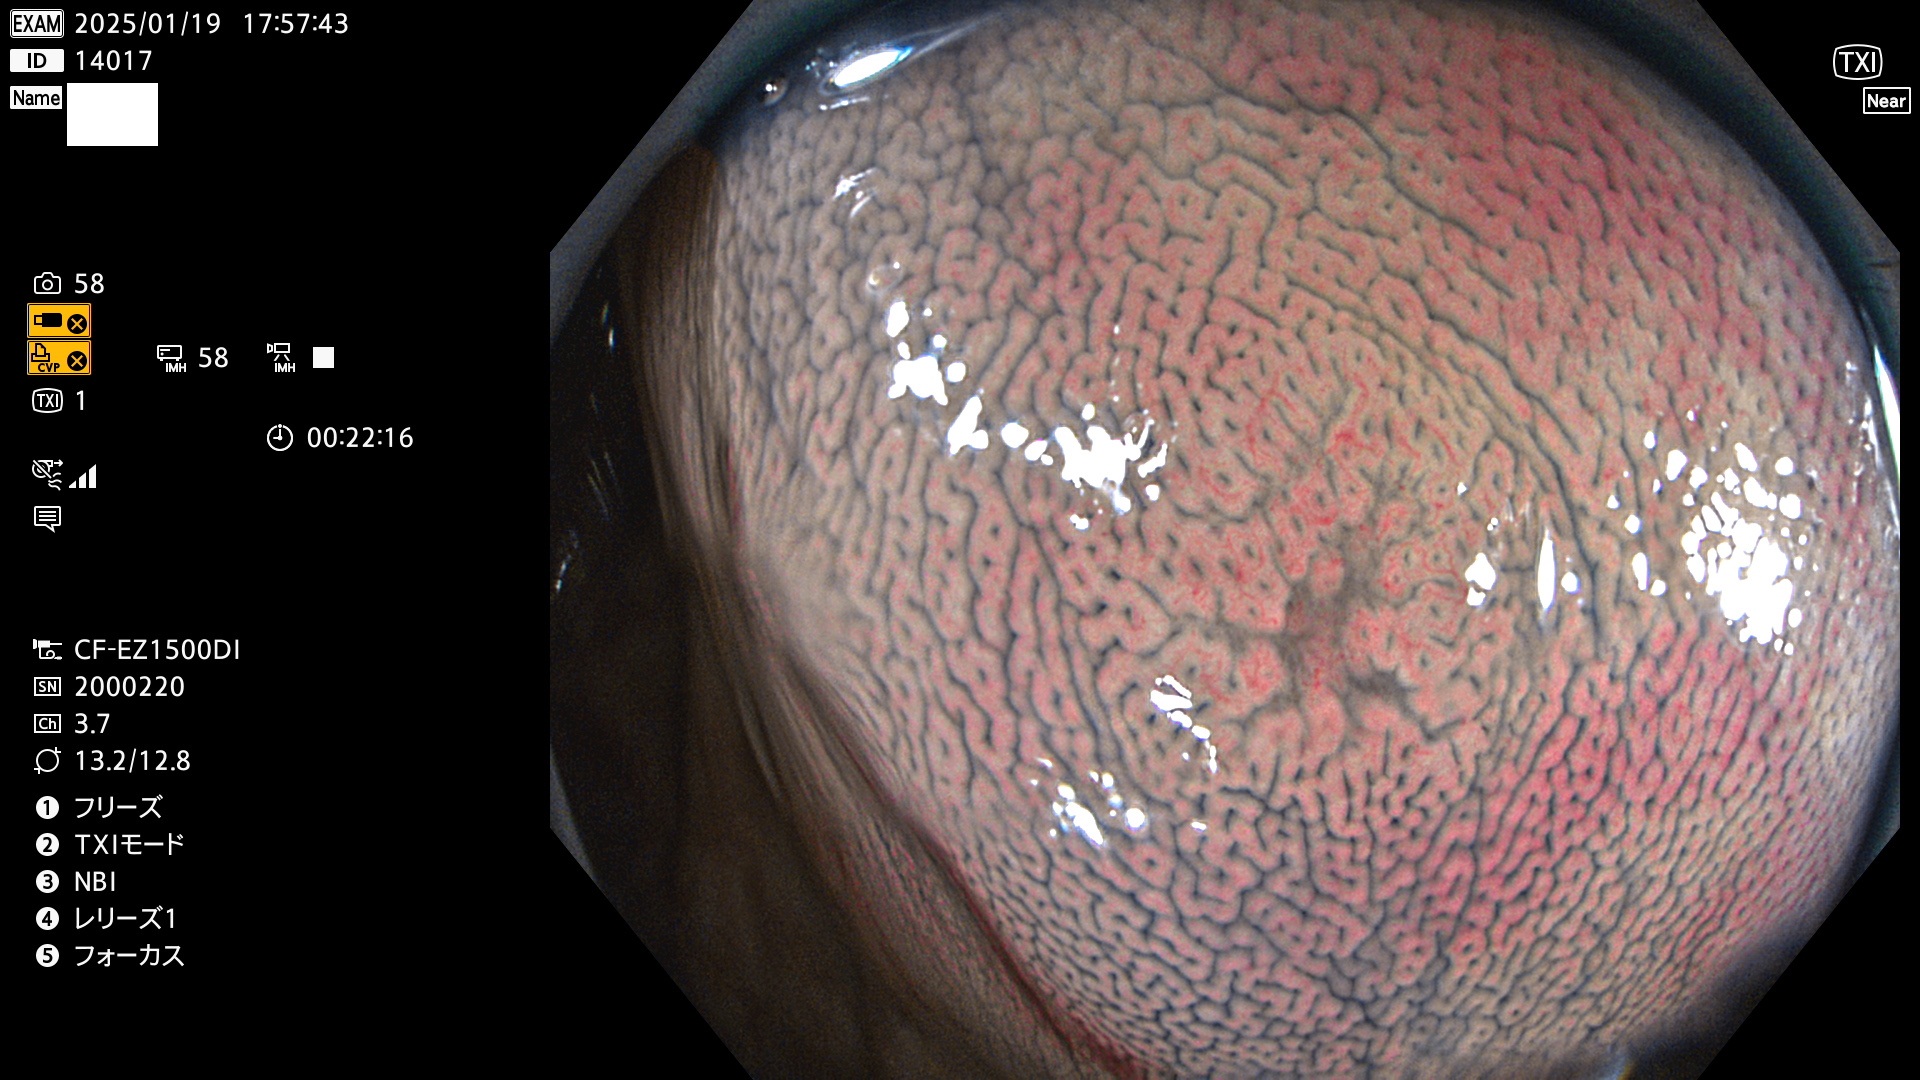

完全に平坦な物をUb、陥凹している物をUcと呼びます。最も発見が難しく危険な病変です。

毎週の検査(木・金・土・日)に発見されたUb、Uc型・腺腫を、その週の日曜の夜にUPし1週間、提示します。

抽出の対象期間 2025年1月16日〜1月19日の4日間(45件の検査)8個 (8/45=17%)